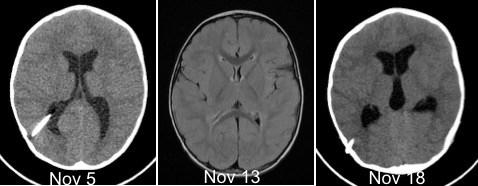

sur l’IRM, il existe souvent une prise de contraste méningée diffuse qui est le support anatomique des céphalées (cf. image ci-dessus)

le syndrome des ventricules fentes

les ventricules diminuent, ils

deviennent de taille quasi-virtuelle ; de plus, en l’absence des variations physiologiques de pression et de volume, le cerveau devient rigide (il perd sa compliance naturelle). lorsque la valve s’obstrue, les ventricules vont donc peu augmenter de volume, ils pourront donc sembler de taille normale si on ne dispose pas d’un scanner de référence pour comparer.

parfois, on constate une évolution cyclique en rapport avec un cathéter fonctionnant

« par éclipses » : l’yperdrainage vide les ventricules, le collapsus ventriculaire entraîne l’obstruction du cathéter, la pression remonte, jusqu’à désobstruer le cathéter, etc.